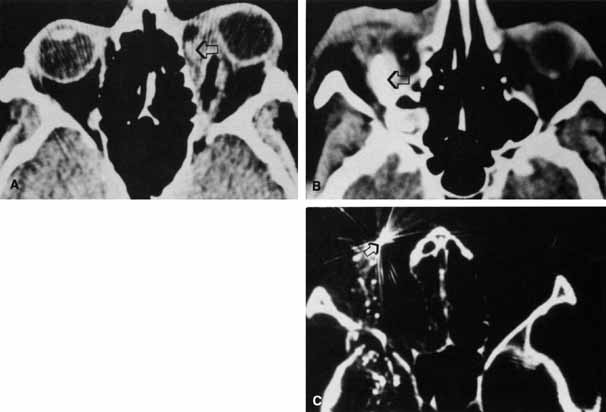

Of the adjunctive tests available, CT scan is the most useful in providing information about the presence and position of a foreign body relative to other structures in the orbit. Steel fragments 0.5 mm in diameter or larger74 and steel particles as small as 0.06 mm3 can be detected.75 Density measurements can be analyzed to distinguish metal, wood, glass, and air from surrounding tissue (Fig. 18). The appearance of wood may vary with the length of time in the orbit and the degree of hydration.76 In some cases, CT has not been able to detect wooden foreign bodies.77 Localization can best be achieved with the evaluation of axial and coronal views. Additional sagittal interpretations and three-dimensional reconstructions can be generated with available software.74 The diagnostic limitations of CT scans must be recognized; in some situations, accurate localization may be obscured by scatter artifact caused by metals or false-negative findings of radiolucent materials.

Fig. 18 A, Wood foreign body (arrow). B, Glass foreign body (arrow). C, Metal foreign body (arrow).